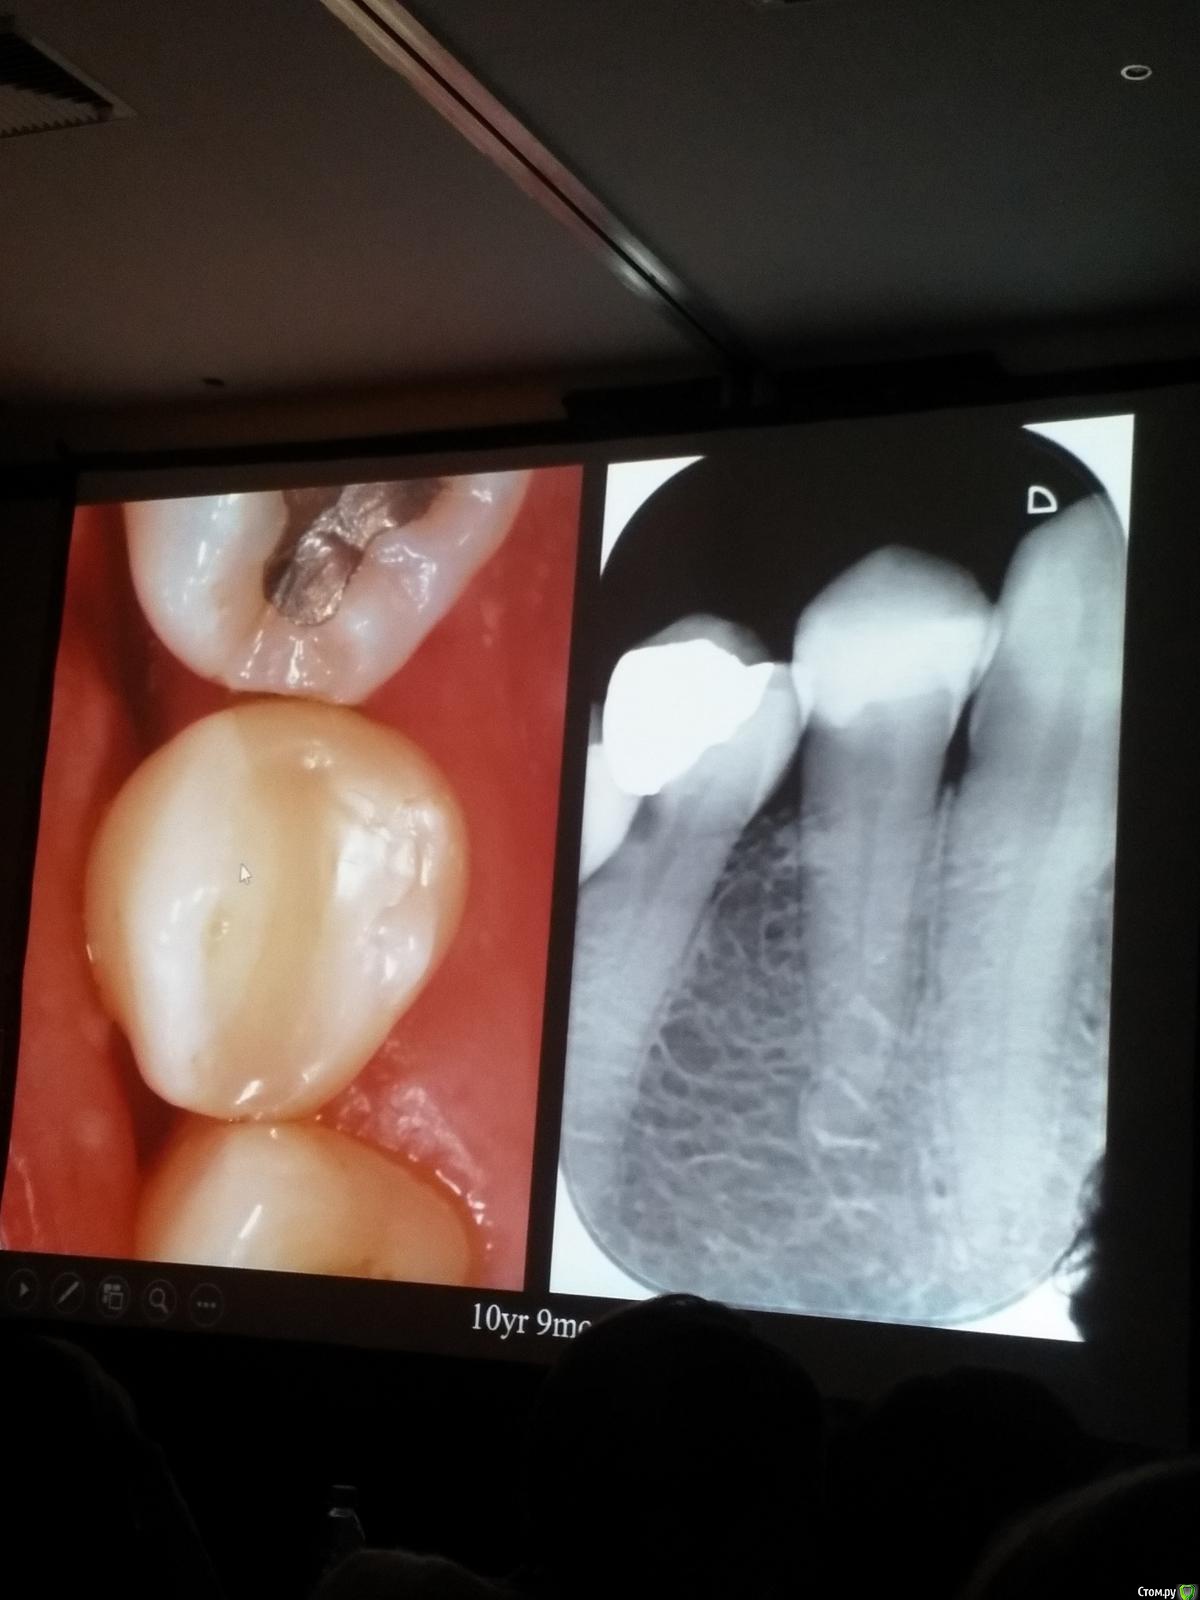

Популярный пост Kolchanov Опубликовано 11 марта, 2017 Популярный пост Поделиться Опубликовано 11 марта, 2017 (изменено) Товарищи, скажу я вам...........Вкратце. Может я где-то что-то и приврал, надеюсь, кто еще был, поправят. Честно говоря немного прибалдел от уровня Доктора. Очень, очень высоко! Приедет еще раз, пойду еще. 1) Фиссуры зондирует острым зондом и выпиливает все дотла. По факту у него уже пломбы, а не герметизация.2) Bite-wing у первичных пациентов всегда.3) Если кариес диагносцирован, то лечить его, пофиг какой он там. Эмали, дентина…4) Препарирует до твердого (или до вскрытия J ). CAD, СID… в топку. Кариес маркером не пользуется, проверяет острым зондом/экскаватором. Вычищает все дотла. Считает, что даже небольшое количество бактерий в дентине под пломбой вызывают хроническое воспаление в пульпе. С его слов у него на контроле где-то 500 вскрытий, не удивительно при таком подходе к очистке.5) Тщательная изоляция. Коффер порвался – меняет. Большое значение герметичности реставрации. под замену6) Критерии обратимости и необратимости.Гистологически, обратимый тот, что без абсцессов в пульпе, но клинически это понять нельзя, только предположить.Здесь был бы обратимый, если бы не удалил. Нет микробов в пульпе. Линия - граница обработки.Покрытие 27 лет назад. Dycal, СИЦ, композит. От дайкала одно воспоминание.7) Вскрылись. Размер перфорации, возраст и прочее не играют роли, важно только состояние пульпы, т.е. диагноз.Примеры перфораций.8) Кровотечение останавливает стерильным ватным шариком. Если останавливается, то покрытие, если нет, то пульпотомия или пульпэктомия.9) Использует гидроокись кальция (порошок), перекрывает Dycal или СИЦ. Потом восстановление Нередко под IRM, потом все убирает (через пару-тройку месяцев) и смотрит, что получилось. Порой приходится повторять! Использует и МТА, его тоже убирает.10) Наблюдение 6мес, 1 год, 2…. Все может провалиться и через месяц и через 24 года.Примеры проваловНиже - 24 года спустя появилась дуля. 11) Неравномерная облитерация полости зуба на RG (после покрытия) – признак текущего хронического воспаления, где-то остались микробы. Рекомендует эндо.12) Мостик который образуется – это не дентин! И одонтобласты не регенерируют и новые не образуются. Что это такое он и сам не знает, но раз это твердые ткани, то и наплевать.Вот фиолетовое это дентинные опилки вмурованные в розовую ткань бог знает кем сформированную.13) Пульпотомия в зубах с несформированной верхушкой и в сформированных, при подозрении на частичное поражение коронковой пульпы. Иссекается стерильным алмазным бором часть пульпы, гидроокись, временная пломба на 90 дней, после повторное раскрытие, оценка результата, восстановление в случае формирования твердых тканей. Гипохлоритом можно мыть, можно не мыть, если мыть, то 0,5-1%.14) В апикальной части пульпа чаще витальна, чем нет.15) Периапикальные поражения возникают по причине поступления токсинов микробов с током крови, а не самих бактерий.16) За апикальные расширения в полностью некротических случаях. Надо механически отодрать биопленку и срезать инфицированный дентин. На ирриганты надежды мало.17) Биопленка на поверхности в 6% случаев.Синенькие пид@расы18) Обработку проводить нежно, краун-даун. Чередовать с H-файлом, чтобы посмотреть докуда распространяется некроз.19) Патенси в витальных кейсах не колоть, сохранять витальную пульпу в констрикции!Формирование еще большего сужения в констрикции за счет сохранения витальной пульпы. Изменено 11 марта, 2017 пользователем Kolchanov 31 Ссылка на комментарий

Популярный пост Kolchanov Опубликовано 12 марта, 2017 Автор Популярный пост Поделиться Опубликовано 12 марта, 2017 Второй день.1) Дезинфекция зуба и раббер дама перед работой. Вначале установка системы, потом протирка тампоном 30% перекиси, потом протирка всего йодинолом. Потом преп, потом повторение и только потом доступ к к/к. Все старые реставрации надо убрать, кариес убрать, противник лечения через коронку.2) Гидроокись на неделю. Замешивает на стерильном физрастворе. При необходимости повторяет. Т.е. в случае сохранения свища, симптоматики, экссудации, запаха. Если свищ не исчезает после трех смен временных вложений, то хирургия.3) Пломбирует латеральной компакцией. Лучше контроль длины обтурации.4) Высушивание канала стерильными штифтами, на рабочую длину минус 1мм. После высушивания штифт оставляется на 60с. в канале и должен выйти сухим.5) Определение рабочей длины. Витальные случаи. АЛ должен три раза дать одну и ту же картинку в определенной точке + проверка RG. Девитальные случаи. На АЛ полагаться сложно, т.к. из-за наличия резорбции констрикции может врать, больше ориентируется на RG.6) Использует ЦОЭ силеры. Резорбируются при незначительном выведении. Резорбируются в канале, позволяя закрыть апекс цементоподобной тканью. Вот так вот.Случаи исчезновения силера, как за пределами канала так и в канале7) Выведение материала (не важно какого) в большом объеме способно вызвать защитную реакцию тканей. Которая должна пройти спустя некоторое время. (иногда это будет 25 лет J Случай 1ый. Студенты наломали инструментов. Периодонтит на RG через год. Резекция и гистология. Бактерий не обнаружил. Да, маленькое замечание. Каждый препарат дает 500-600 срезов. И ищет он на всех. Объем работы, конечно….Случай 2й. Его собственный. Периапикальное поражение, обнаруженное на реколле через 10 лет зажило еще через 15.8) «Функционирующий зуб» считает результатом неприемлемым. Осталась инфекция с которой надо что-то делать. То, что бактерий можно замуровать в дентинных трубочках и под пломбировочным материалом, считает неправильным. Продукты метаболизма один фиг будут просачиваться и могут поддерживать реакцию воспалительную.Случай. Синее – маленькая кучка микробов, предположительно, препятствовавших заживлению очага.9) Биопленка на поверхности корня может принимать вид кальцификатов (камней) и тут уже только хирургия в помощь. При длительном существовании свищевого хода, например.Черное - это камни вокруг апикального отверстия. И гистология их с кучей синих микробов.Здесь камни на фуркации и отсутствие заживления и свищ даже после ретроградной обработки и пломбировки.А здесь вообще чертова уйма камней. И зацените разветвление канала в этом боковом резце (последнее фото препарата). 10) Реваскуляризация.В некротических случаях дентина не образуется, т.к. одонтобластов нет и не будет новых. Образуется та самая бог знает какая ткань, которая даже и с корнем не связана может быть. Суть здоровый дентикль-петрификат. А в витальных это не реваскуляризация, а обычное формирование корня. Так что нечего тут.11) Трещины дентина.Советует расшивать, братья и сестры. Без фанатизма, если нет симптоматики, но, по возможности максимально. Если есть симптоматика, то там уже по обстоятельствам. Чертова уйма микробов там и ползет, ползет к пульпе. Надеюсь, что еще раз этот замечательный Доктор приедет. Схожу с удовольствием. 2 23 Ссылка на комментарий